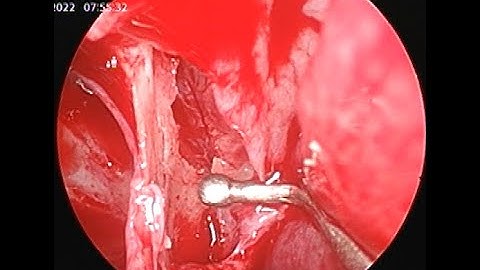

Epistaxis cauterization